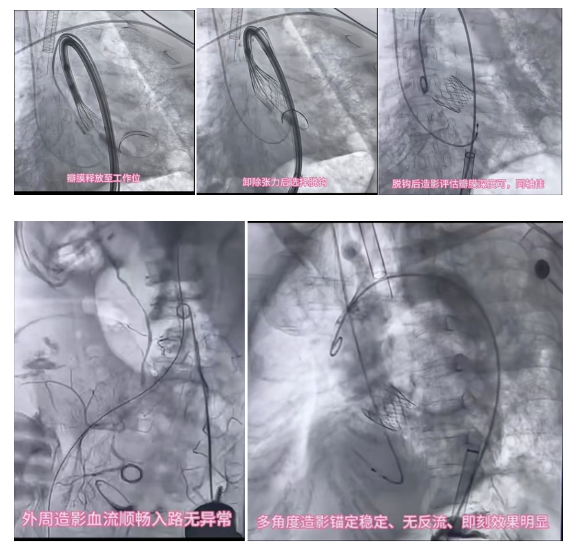

在全院统筹协调下,手术麻醉、重症监护、输血等多学科紧密配合下,心脏中心团队在 DSA 复合手术室全麻下为患者实施经导管主动脉瓣置换术(TAVR)+ 股动脉缝合术,同时由王忠明副院长全程备台,一旦术中出现突发情况可立即无缝衔接开胸手术,心内、心外强强联手,最大限度保障患者术中安全。

全程可视化导航: 应用经食管超声心动图(TEE)实时监测双室功能、瓣膜位置及心肌缺血征象,如同为手术装上了「高清雷达」。

此次手术的成功,核心依托于昆明三博脑科医院先进的 DSA 复合手术室平台,以及成熟的心内外科联合、多学科协作诊疗模式。